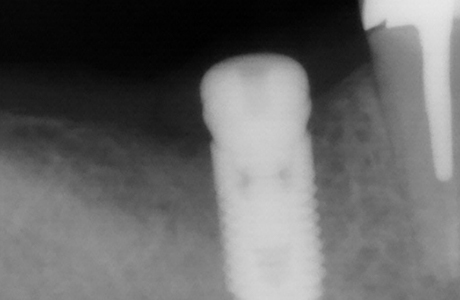

Пациентка обратилась в клинику за установкой зуба, удалённого более года назад, с целью восстановления жевательной функции. Врач стоматолог-терапевт, хирург, имплантолог, ортопед Шандро Евгения Богдановна провела осмотр и анализ компьютерной томографии, после чего принято решение установки импланта Alpha Bio в позицию зуба 4.6.

- установка импланта Alpha Bio;